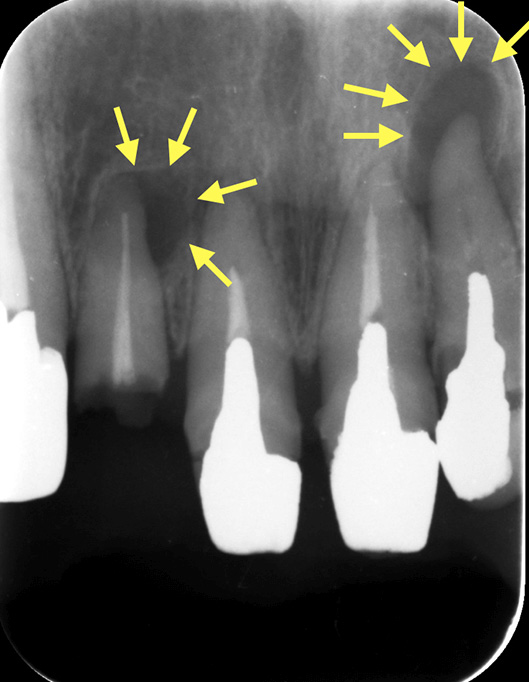

図3すでに根管治療をされた歯が再び感染を起こした場合

歯の根の回りが黒くなっているのが分かる。すでに根管治療をされていても何らかの原因で感染が起こり、歯を支える骨を溶かしている。